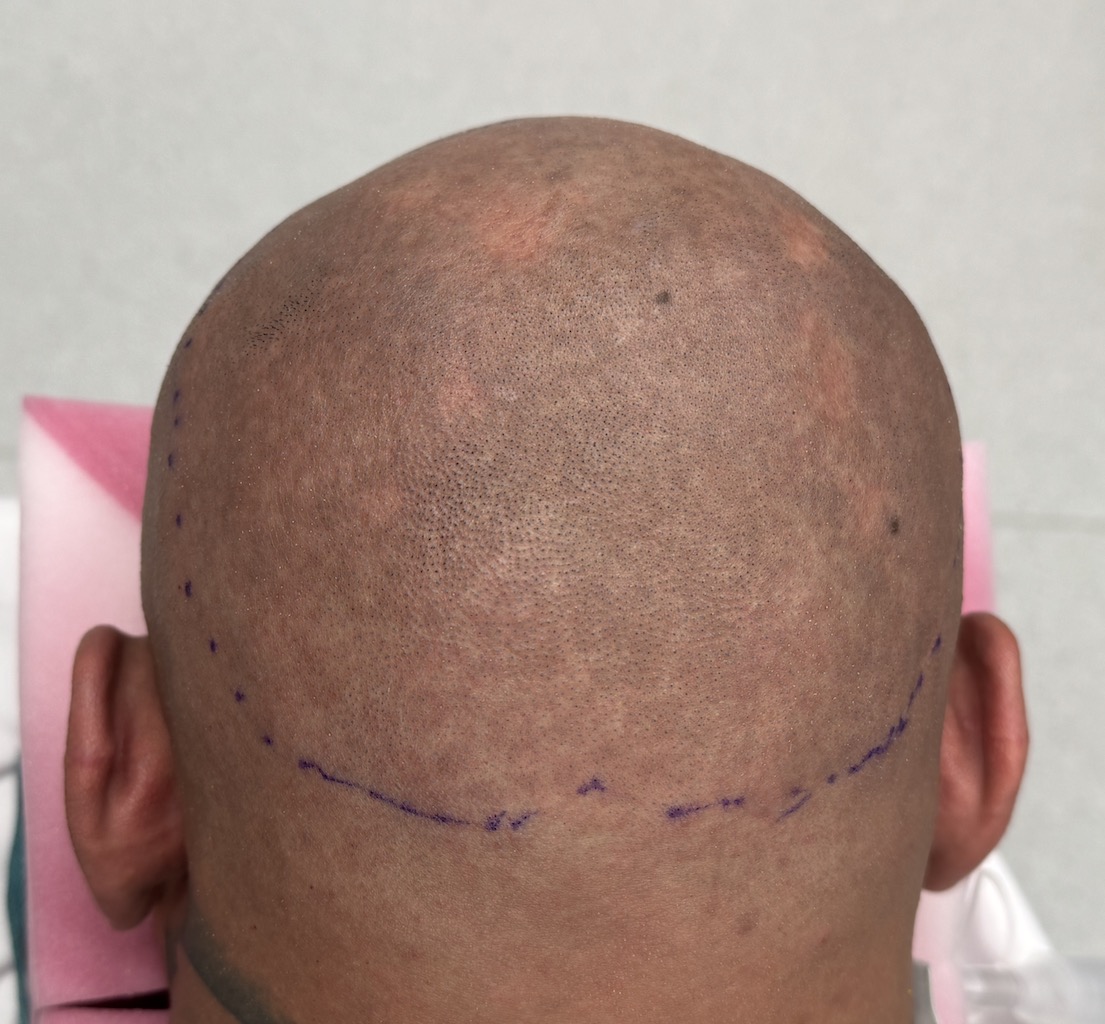

Desire for further skull augmentation after a primary skull implant.

Five years after an initial custom skull implant placement a new custom skull implant that increased the volume by 35% was placed.

Desire for further skull augmentation after a primary skull implant.

Five years after an initial custom skull implant placement a new custom skull implant that increased the volume by 35% was placed.